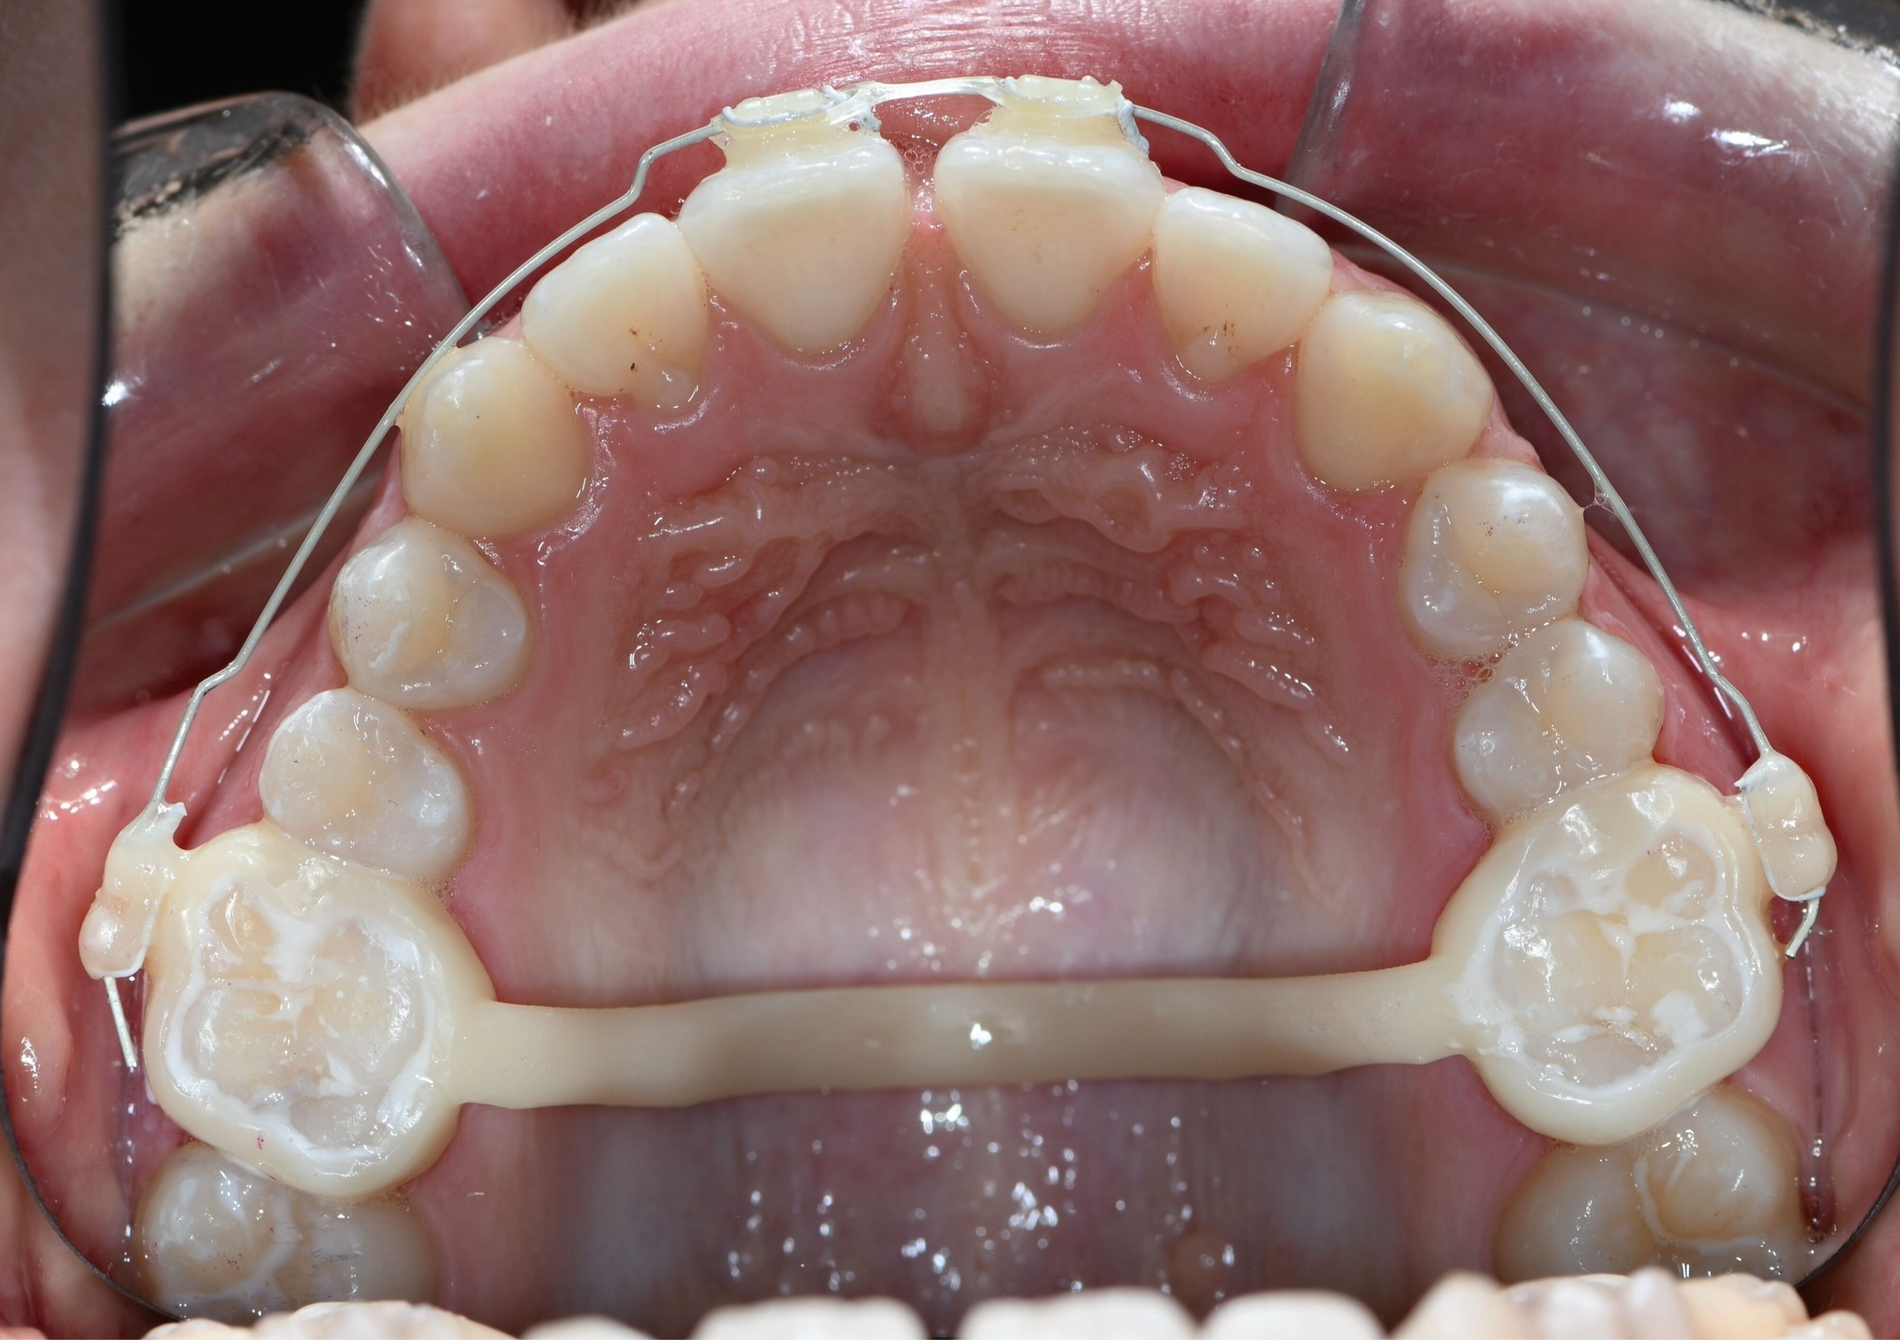

Multibracketapparatur

Auch die Herstellung zusätzlicher Elemente, wie beispielsweise Transpalatinalbögen aus Keramik-gefüllten 3-D-Druckkunststoffen, ist möglich (Abbildung 2c) [Thurzo et al., 2022], muss jedoch in großangelegten Studien noch auf eine ausreichende klinische Suffizienz untersucht werden. Weiter bieten 3-D-gedruckte Transferguides die Möglichkeit des „Indirekten Klebens“ [Deahl et al., 2007; Bozelli et al., 2013; Li et al., 2019; Sabbagh et al., 2022], wobei die Bracketpositionierung bereits vor dem Einsatz digital festgelegt und schließlich durch den Transferguide intraoral übertragen wird (Abbildung 2d). Neben einer verkürzten Stuhlzeit erlaubt dieses Verfahren eine besonders hohe Genauigkeit der Bracketpositionierung.